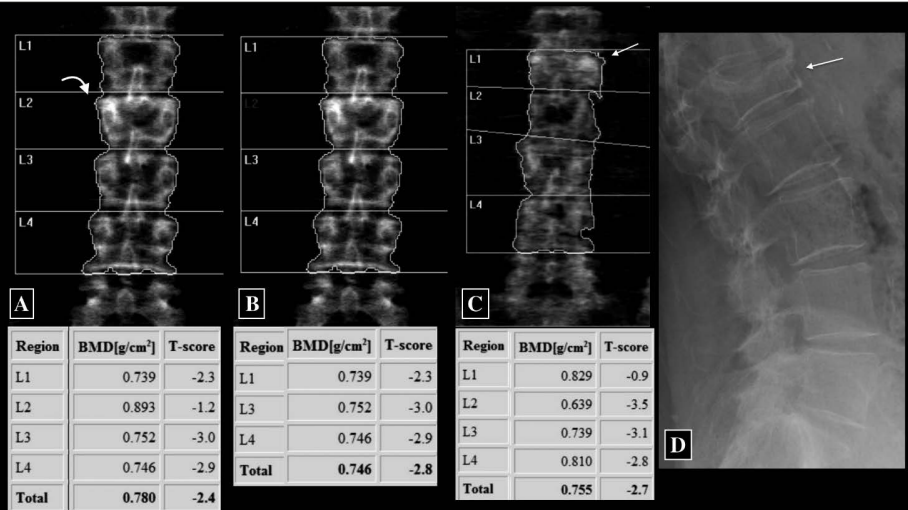

Una vertebra deve essere esclusa se è presente una frattura, un’alterazione strutturale grossolana (come un emangioma o esiti chirurgici) o se il suo T-score differisce di oltre 1.0 DS rispetto alle vertebre adiacenti.

Artefatti degenerativi e calcificazioni

Dopo i 65 anni, la colonna lombare diventa spesso inaffidabile per la diagnosi a causa dell’artrosi.

Gli osteofiti, la sclerosi delle faccette articolari e le calcificazioni dei legamenti vengono proiettati nell’area di scansione e aggiungono “massa minerale” che non appartiene al corpo vertebrale, portando a un T-score falsamente elevato.21

Allo stesso modo, le calcificazioni dell’aorta addominale, visibili come formazioni radiopache davanti alla colonna, contribuiscono alla sovrastima della BMD.

In questi casi, la valutazione del femore prossimale è considerata più accurata per la diagnosi di osteoporosi sistemica.